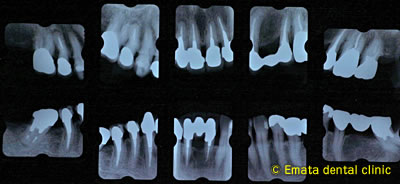

治療前

レントゲンでは全体的に歯を支えてる骨がだいぶ喪失しています。重度の歯周炎です。